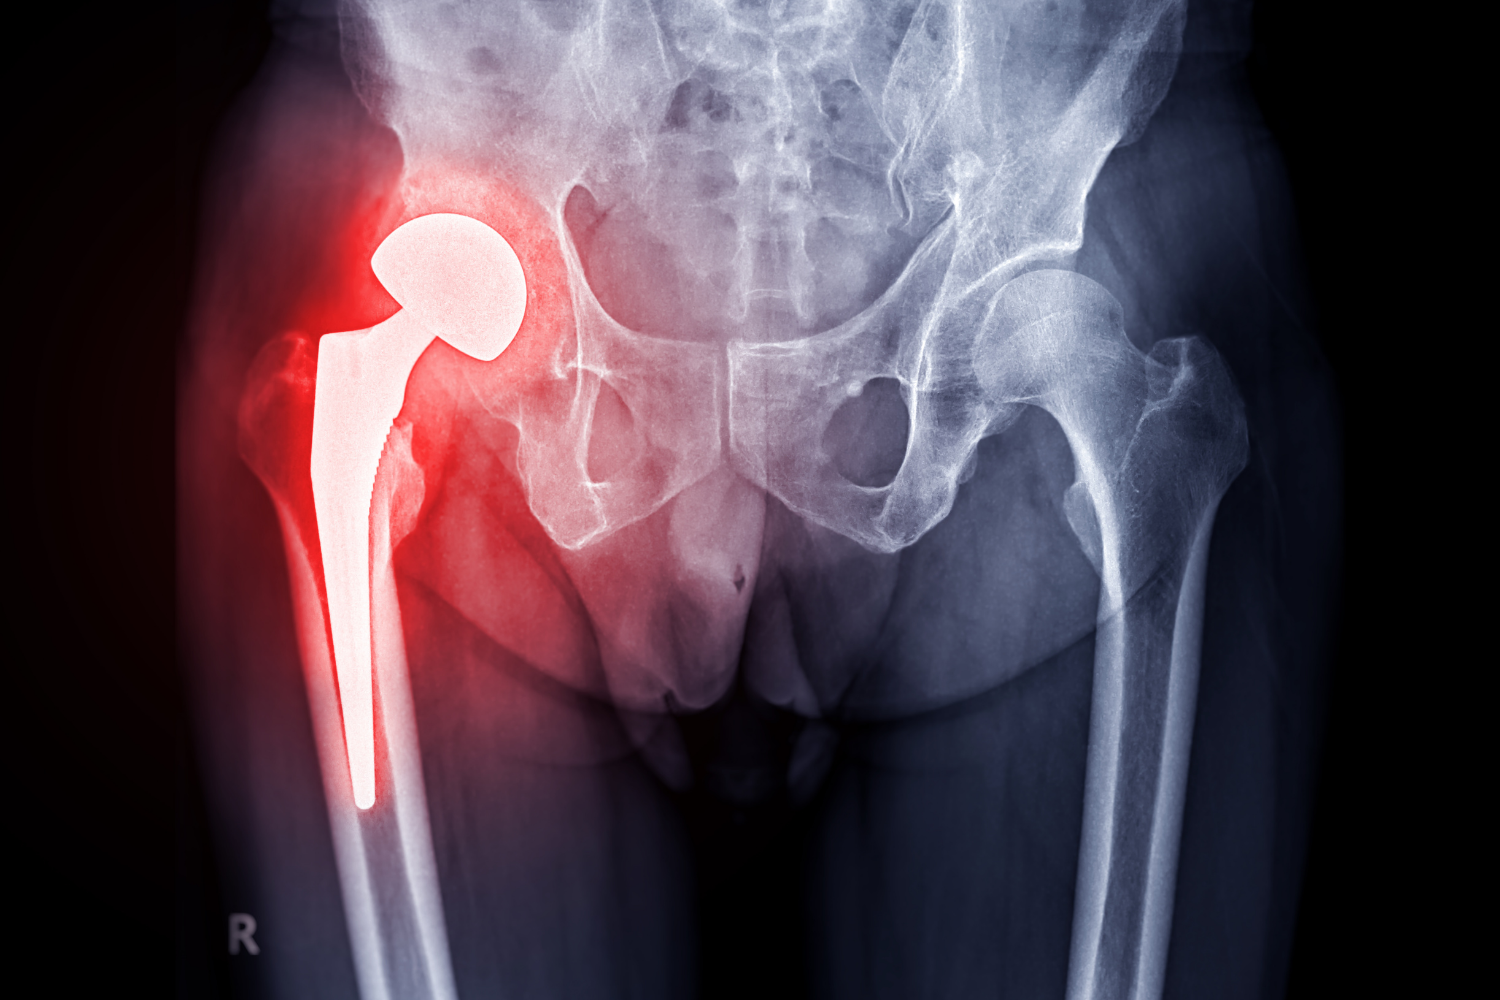

Cirugía de Prótesis de Cadera Clínica GSTAR

Prótesis de Cadera

Vuelve a disfrutar de una vida activa con nuestra prótesis de cadera. Confía en nuestra experiencia para brindarte una solución duradera y mejorar tu calidad de vida.

Artrosis y Prótesis de Cadera

Todo sobre el reemplazo articular para recuperar la calidad de vida en adultos mayores.